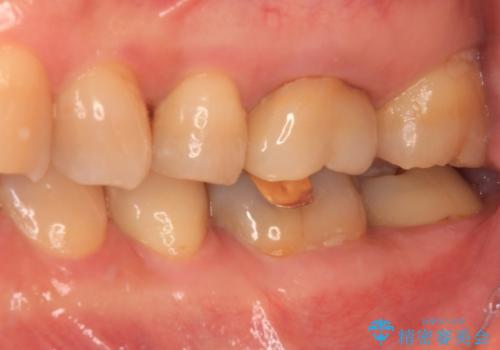

境目にものが詰まって気になる オールセラミッククラウン治療

- 奥歯に装着したクラウンの周りに汚れが溜まりやすいとのことで来院された患者様です。

既に装着されているクラウンの質は決して悪いものではありませんでしたが、患者様自身が非常に気にしていたため、作り替えの治療を行うこととしました。

クラウン装着後は、特にものが挟まる感覚もなく、快適に過ごすことができるようになりました。